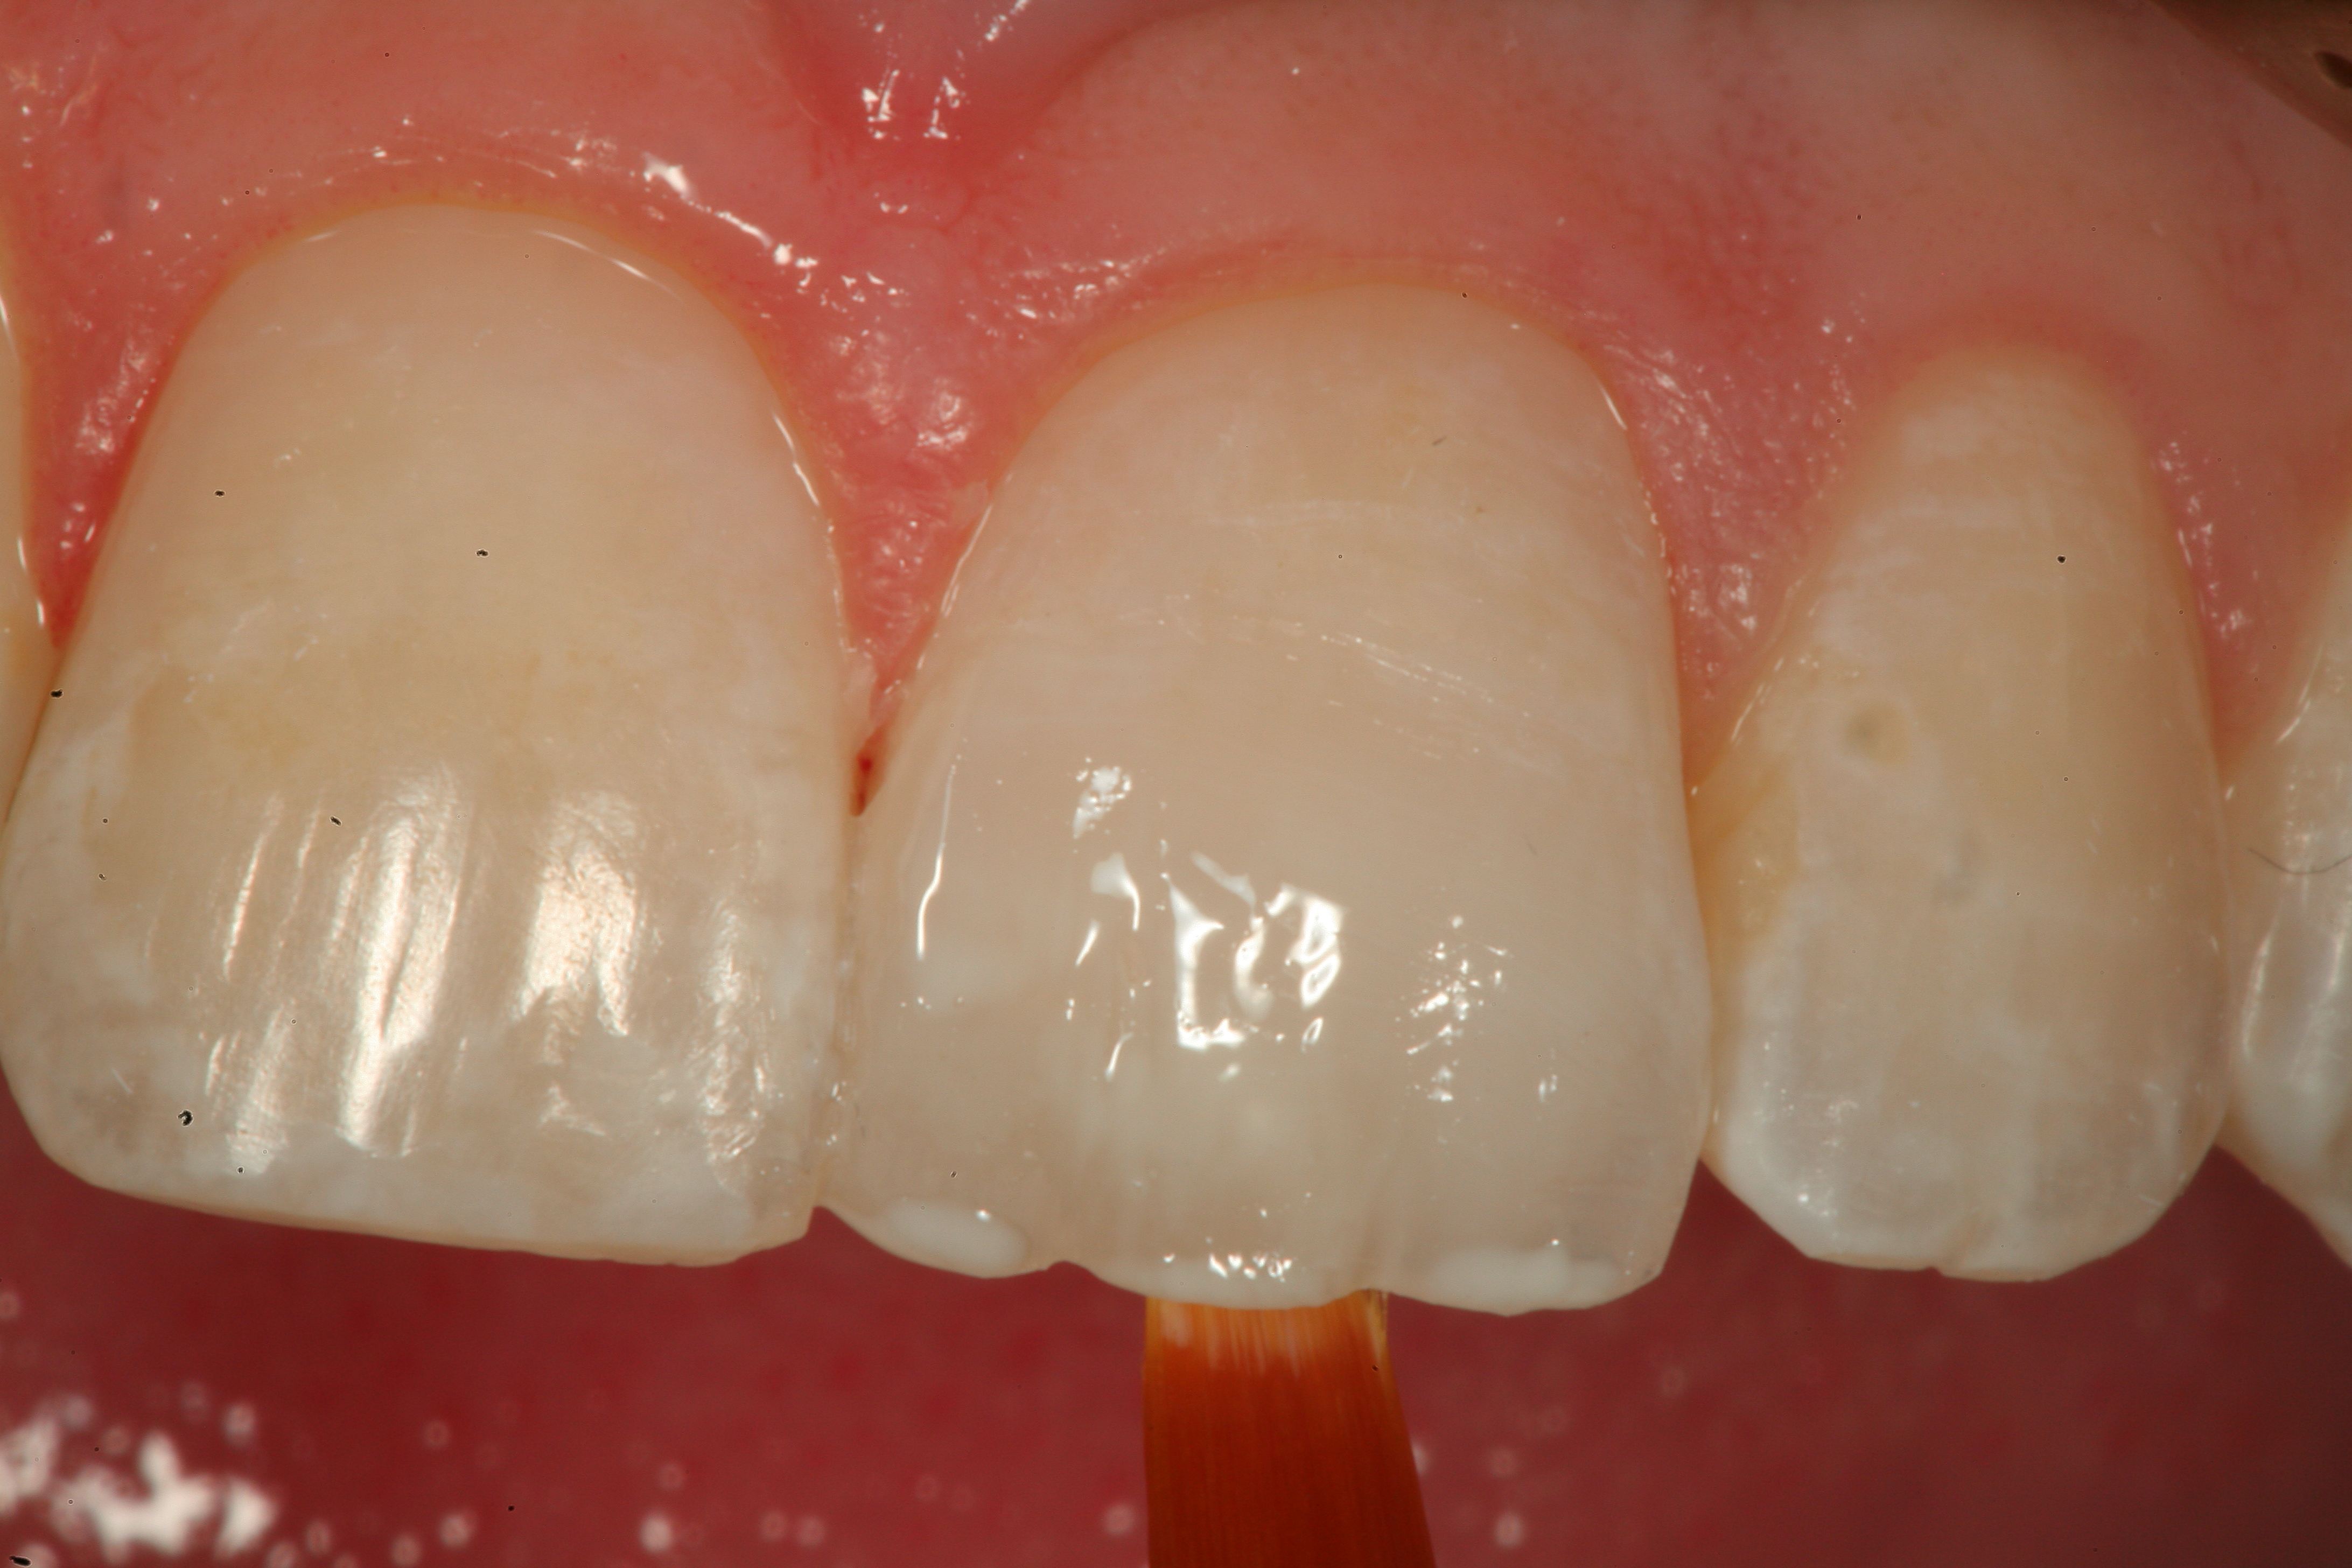

Fig 12. A Class IV mesial incisal fracture is shown from the facial aspect on tooth No. 9.

Figure 12